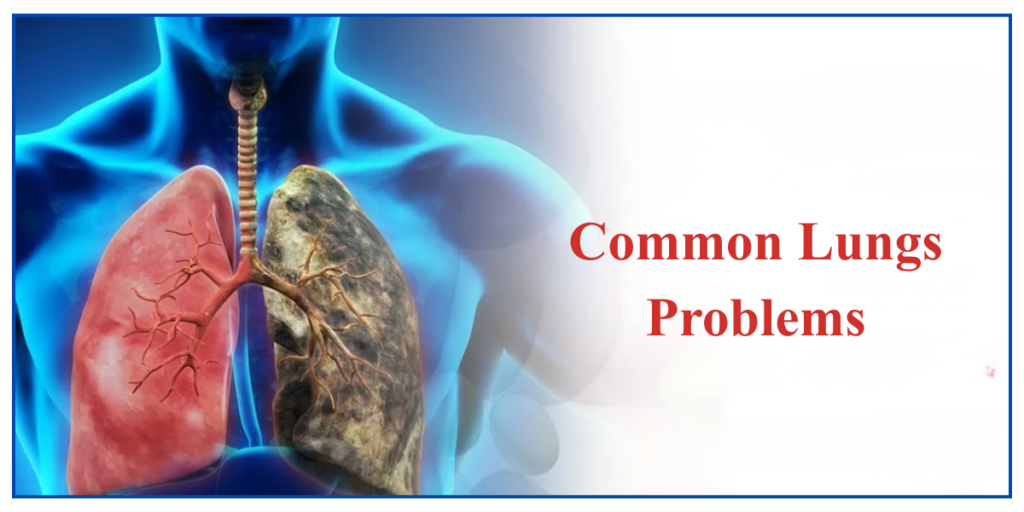

Lungs Problems – The lungs function as vital organs, which allow humans to breathe by delivering oxygen to the body while simultaneously eliminating the carbon dioxide.

In today’s world, people face an increased risk of lungs diseases because of three main factors, which includes pollution, smoking, and their existing health conditions.

This article explained the early diagnosis of lungs problems together with improved prevention methods, can be achieved through an understanding of their typical symptoms and main underlying causes.